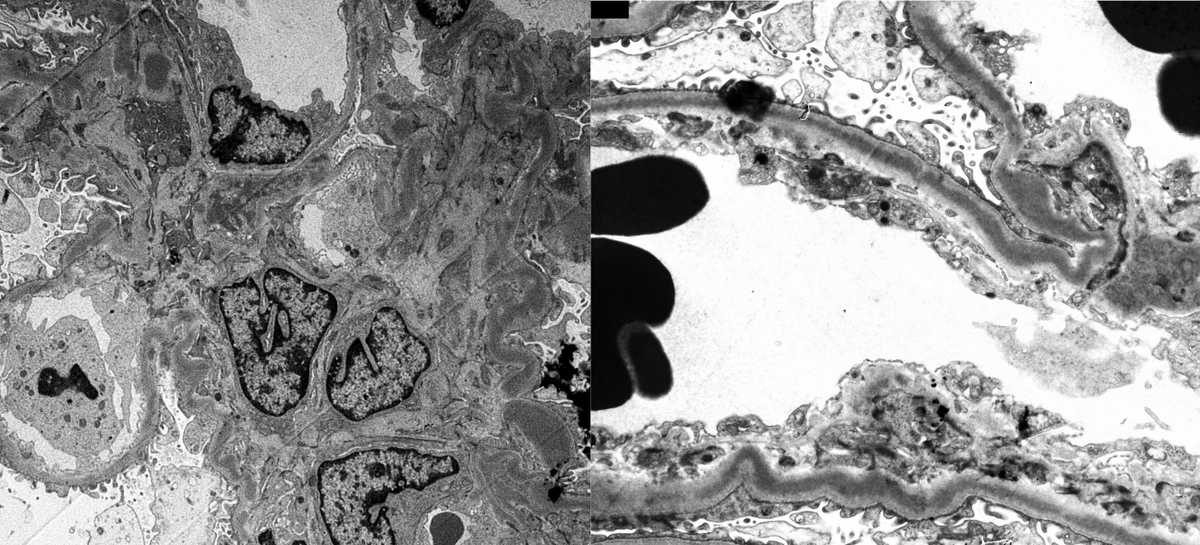

Older pt w/DN, MGUS. Worsening renal function + proteinuria. Bx: mildly active endocapillary proliferative GN + segmental fibrous crescents. IF: C3 only. k/L (-). EM with fusiform intramembranous deposits: Dense deposit disease (monoclonal Ig associated). #renalpath #twitterpath